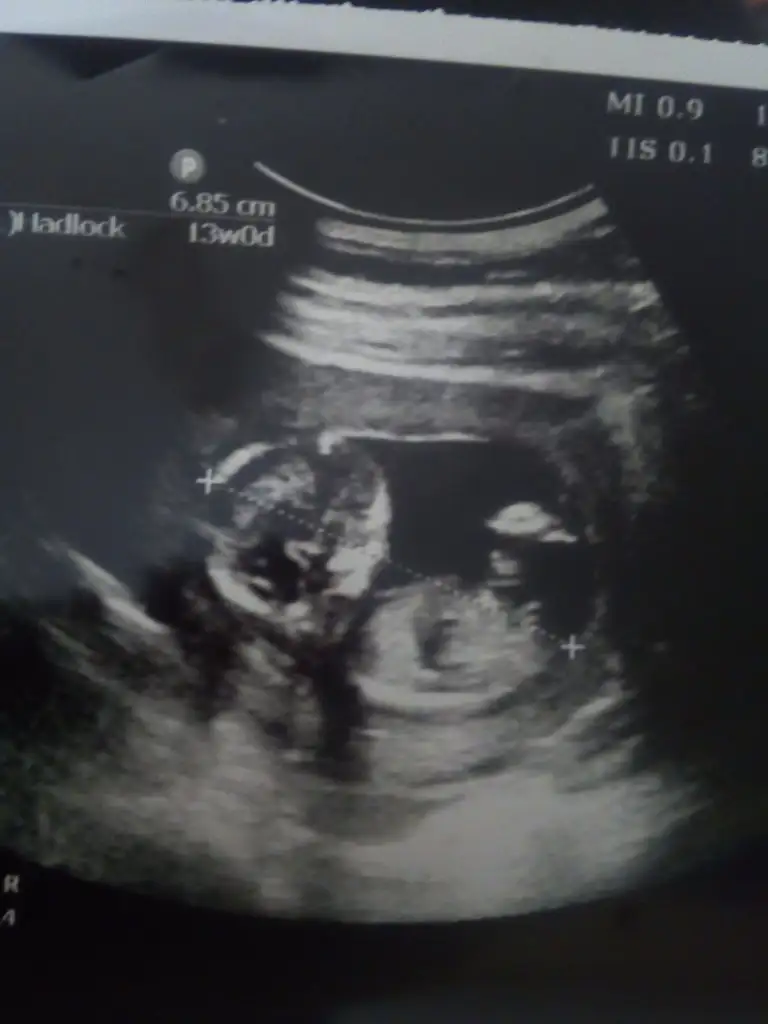

Teşekkür ederim ,doktorumuzda erkek dedi :)Erkek görünüyor

O ayak nub ve popo acısi önemli onu hesap etmek lazımdik olan nub mu acaba

USG yarım bebeğin alt tarafı almamış drBayanlar tahmin